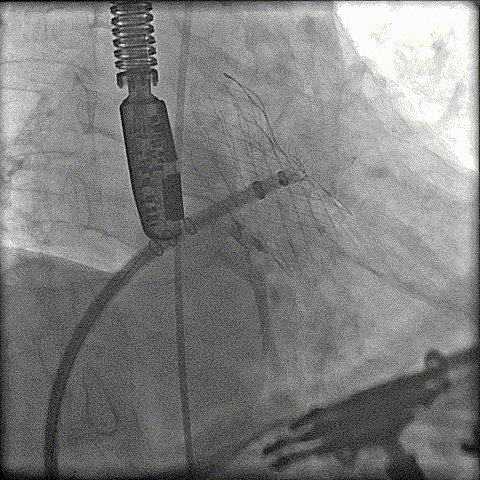

封堵器缓慢展开

即刻造影

释放封堵器

术前CT分析判断该心耳为反鸡翅型左心耳,选择偏下略偏前的位置进行房间隔穿刺。在工作体位造影后,可见左心耳内梳状肌发达,反鸡翅叶显影清晰,鞘管轴向佳。经DSA测量左心耳开口18mm深度17mm,结合TEE测量数据,综合考虑选用WATCHMAN24mm封堵器进行封堵。在展开封堵器时利用在体内借深度技巧,保证封堵器封堵位置合理。封堵器展开后经造影检查封堵器封堵效果理想,牵拉试验稳定。超声评估封堵器各角度无残余分流,位置理想,满足PASS原则,随即释放封堵器,一站式手术顺利结束。